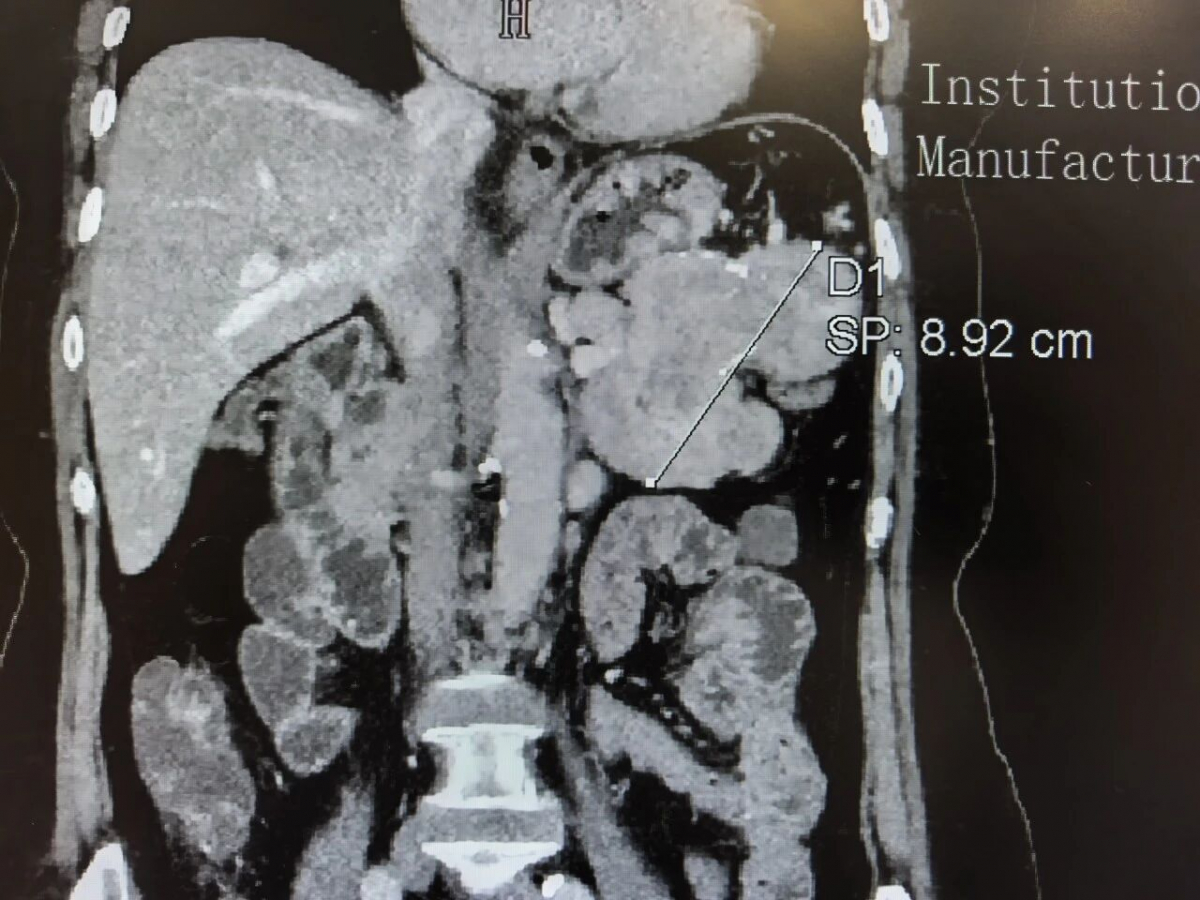

患者因“间断腹痛2个月、加重2周”来到国家区域医疗中心普外科就诊。起初仅上腹隐痛,未予重视,近两周疼痛加剧,影响饮食与休息。经医生检查发现,其胰腺体尾部长有一约9×6厘米的占位,初步考虑为胰腺神经内分泌肿瘤,大小约等于成人手掌。由于胰腺位于腹腔深部,周围紧邻胃、脾脏、肾脏和重要血管,不仅会持续引起腹痛等不适,手术中稍有不慎,还可能出现出血,甚至损伤左侧肾脏供血血管,因此手术难度大、风险高。

患者胰腺CT